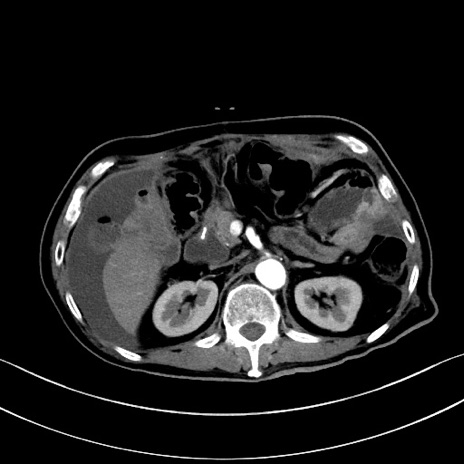

冠状断像

【症例】60歳代男性

【主訴】嘔吐

【現病歴】胃癌にて胃全摘後。食思不振が悪化し、夜中に嘔吐することがある。

【既往歴】胃癌、胃全摘、脾摘、胆摘後

【データ】WBC 5900、CRP 10.56